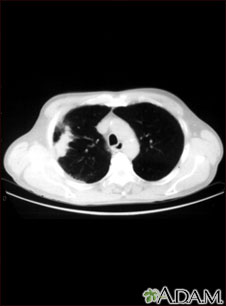

A chest CT (computed tomography) scan is an imaging method that uses x-rays to create cross-sectional pictures of the chest and upper abdomen.

A CT scan quickly creates detailed pictures of the body. The test may be used to get a better view of the structures inside the chest. A CT scan is one of the best ways of looking at soft tissues such as the heart and lungs.